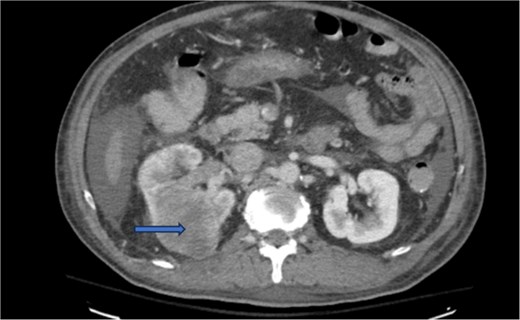

Diagnostic imaging began with a chest X-ray that indicated bilateral pleural effusions. An abdominal ultrasound detected a 4.6 × 4.2 × 4.3 cm echogenic lesion in the right hepatic lobe. Further imaging with a computed tomography (CT) scan of the chest, abdomen, and pelvis revealed a large mass originating from the posterior aspect of the right mid-kidney consistent with RCC (Fig. 1). The mass associated with thrombus extended into the renal sinus and collecting system, traveled along the right renal vein to the inferior vena cava (IVC), and projected into the right atrium (Figs 2 and 3). During hospitalization, bilateral lower extremity pain led to the diagnosis of bilateral deep vein thromboses via duplex venous ultrasound. Echocardiography showed normal left ventricular ejection fraction, impaired diastolic filling, mildly increased ventricular wall thickness, and an echogenic mass extending from the right atrium into the IVC consistent with the tumor thrombus.

CT chest abdomen and pelvis with contrast showing inferior extension to the level of the distal margin of the IVC.